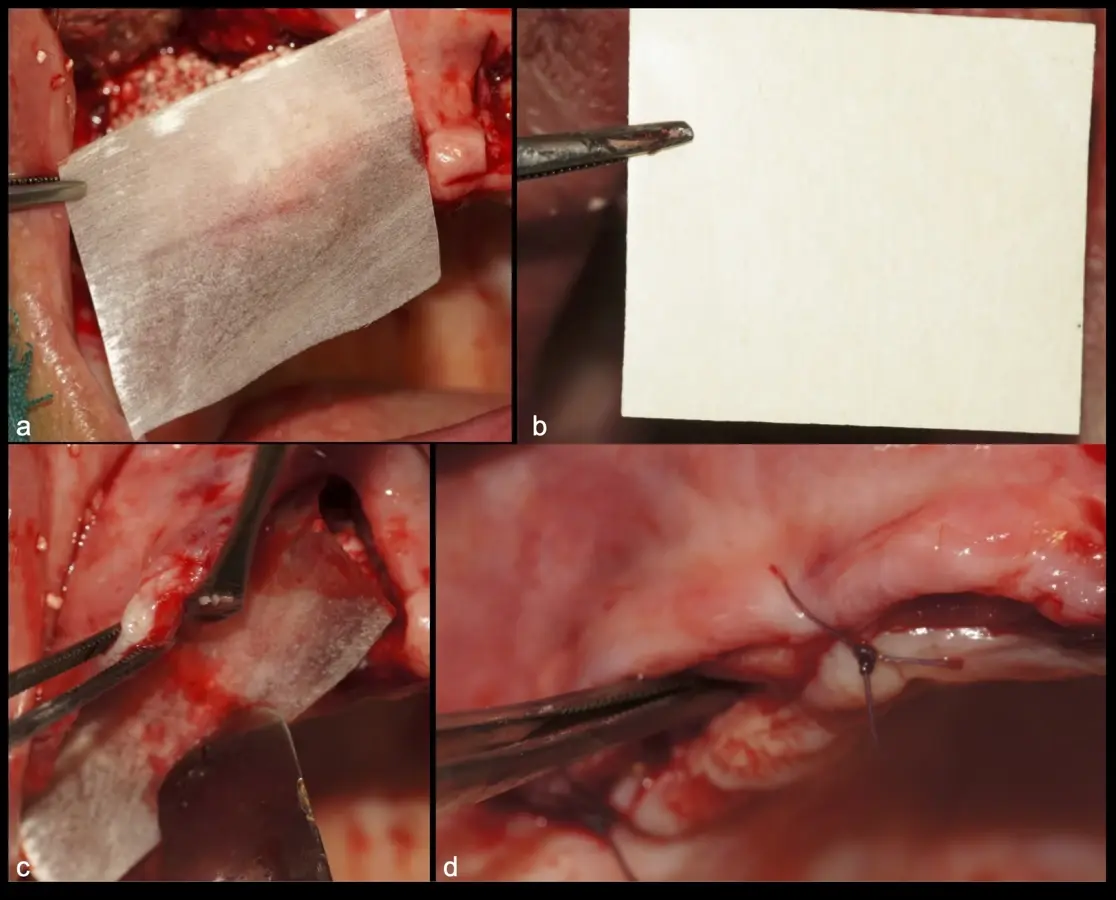

Figura 33. Pasos de la colocación de membranas de barrera y cierre sin tensiones (a - d).

Figura 41. Modelado del bloque óseo con inserto plano de punta diamantada (a) para redondear los ángulos agudos y así evitar una dehiscencia o fenestración de los tejidos blandos (b).

Figura 44. Pasos para la colocación de la membrana de barrera (a - d).

El libro, escrito con Jerson Palomino Zorrilla, Karla Díaz Cavero y María Eugenia Guerrero Acevedo, de la Universidad Privada San Juan Bautista, en Lima (Perú), ofrece la evidencia científica más actual para respaldar el valor clínico de diversos procedimientos con piezoeléctrico, cuya utilidad práctica en el consultorio demuestra mediante la publicación de numerosos casos clínicos.